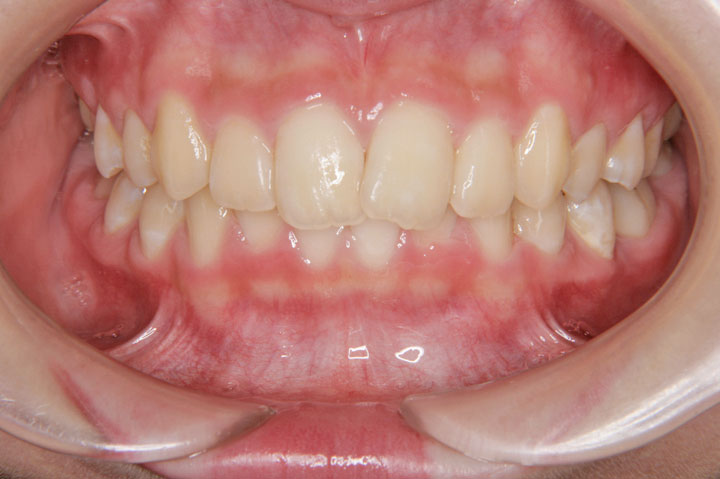

叢生(乱ぐい歯)

上顎前突(出っ歯)

上顎の前突感と前歯のデコボコを主訴に来院された中学1年生の患者さんです。上顎前突と叢生の程度は比較的軽度でしたので、非抜歯でエッジワイズ治療を行っております。顎間ゴムへの協力もよく、プロファイル(側貌)の改善も得られ良好な治療結果となりました